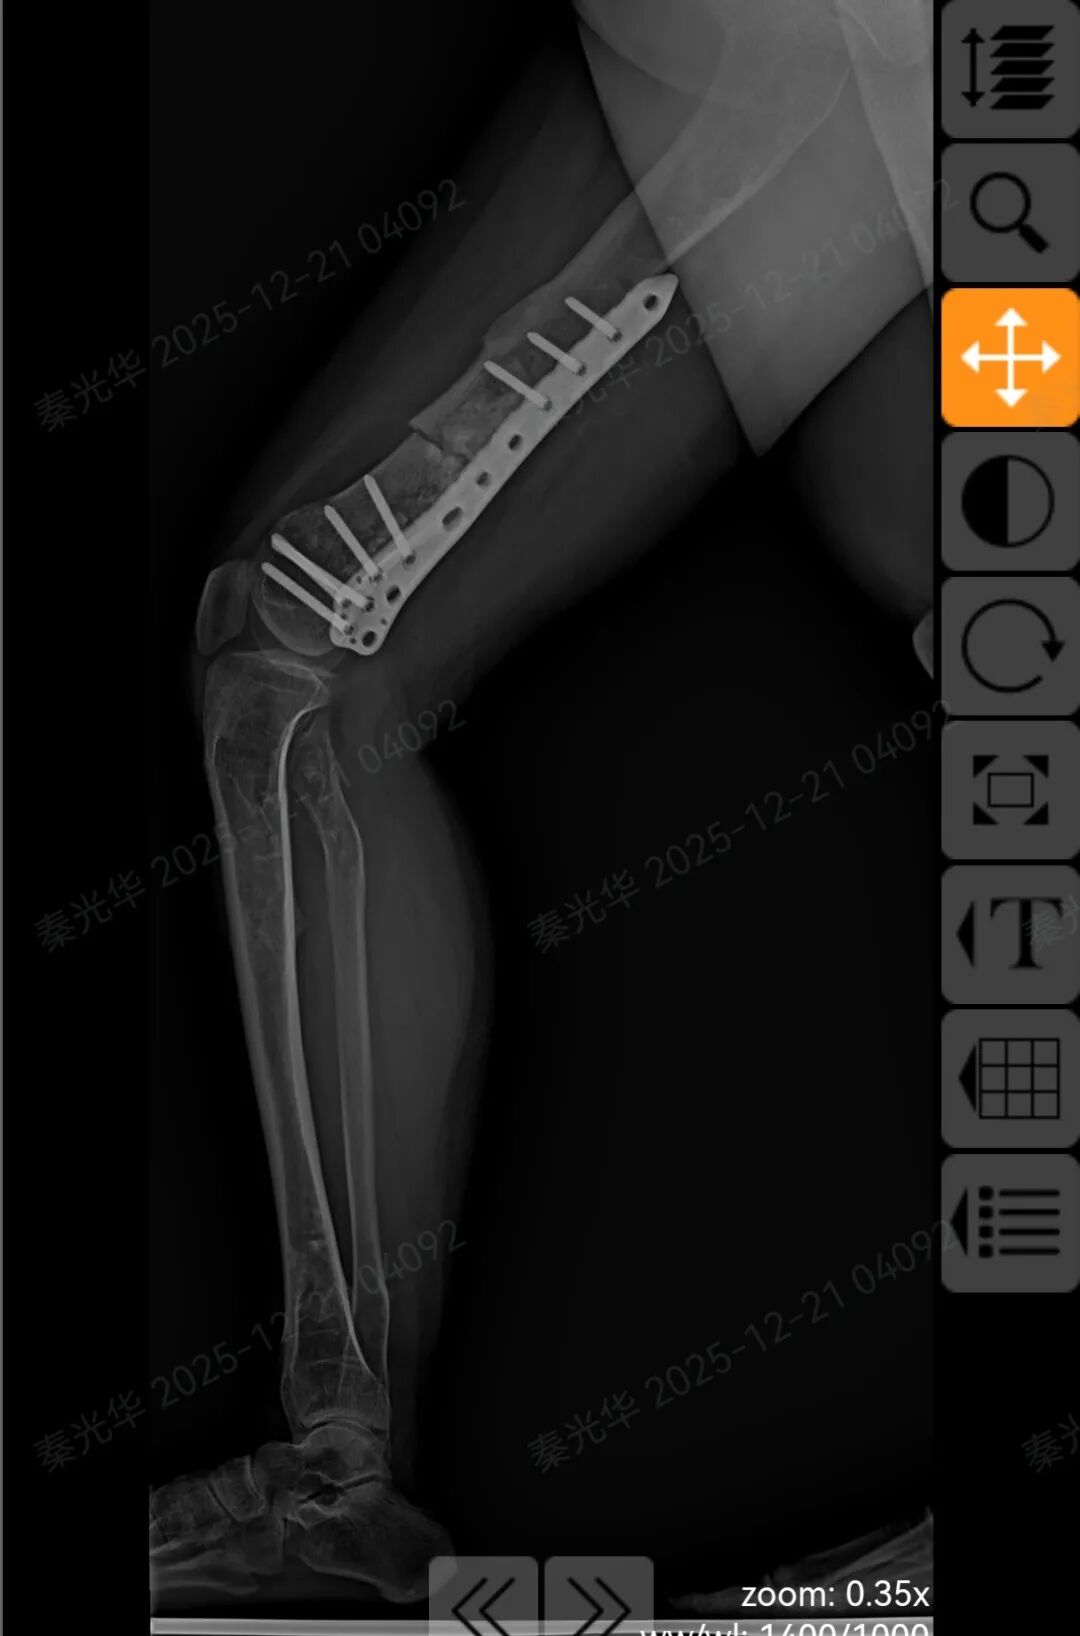

根据X光显示,她右侧股骨畸形突出,双下肢长度差肉眼可见。

患者术前X光片